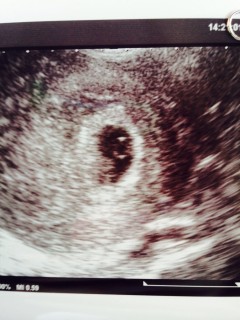

胎芽2.04cm

心拍112BPM

一週間前は何も見えなかったのに、こんなに急成長してくれていました。

妊娠しているんだ!とやっと自覚が芽生えました。

一昨年自然妊娠したけども流産してしまい、AIHまで進んだけども全然できませんでした。思いきって病院を変え、インスリン抵抗性が高いためにメデットを内服したとたんに来てくれました♡心拍も確認でき思わず涙が出ました。無事に出産出来ることを願います。